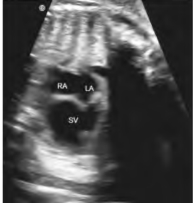

1.22.3三、胎儿先天性心脏病

1.21.10.1一、完全型大动脉转位

1.21.10.2二、矫正型大动脉转位